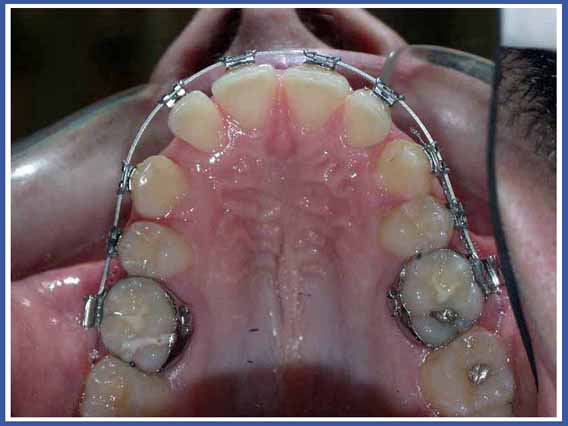

Удерживатель пространства – это маленькое металлическое приспособление, которое подготавливается и приспосабливается индивидуально для вашего ребенка в соответствии со строением его рта. Оно надежно закрепляется во рту и будет снято только тогда, когда постоянный зуб займет правильное для себя место. Это приспособление обычно строится из металлического колечка, приклеиваемого к соседнему зубу, и металлической трубочки, присоединенной к нему и опирающейся на соседние зубы. Целью использования приспособления является стабилизация зубов, оставшихся по сторонам промежутка, а также предотвращение их смещения в сторону этого промежутка до того момента, когда прорезавшийся постоянный зуб займет свое место.

Каким образом сохраняется исправность и чистота удерживателя пространства?

Существует несколько правил, которые Ваш ребенок должен соблюдать для того, чтобы сохранять исправность удерживателя пространства.

Он должен будет избегать сладкой и липкой пищи и жевания жвачки.

Вы должны будете объяснить ему, что нельзя тянуть или толкать удерживатель пространства пальцами или языком.

Нужно сохранять удерживатель пространства в чистоте с помощью зубной щетки и зубной нити.

Вы должны являться на профилактический визит к зубному врачу каждые 6 месяцев.